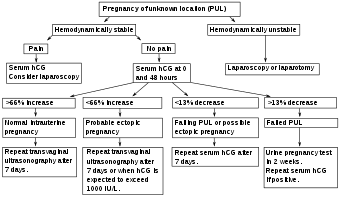

Pregnancy of unknown location

Pregnancy of unknown location (PUL) is the term used for a pregnancy where there is a positive pregnancy test but no pregnancy has been visualized using transvaginal ultrasonography.[5] Specialized early pregnancy departments have estimated that between 8% and 10% of women attending for an ultrasound assessment in early pregnancy will be classified as having a PUL.[5] The true nature of the pregnancy can be an ongoing viable intrauterine pregnancy, a failed pregnancy, an ectopic pregnancy or rarely a persisting PUL.[5]

Because of frequent ambiguity on ultrasonography examinations, the following classification is proposed:[5]

| Condition | Criteria |

|---|---|

| Definite ectopic pregnancy | Extrauterine gestational sac with yolk sac or embryo (with or without cardiac activity). |

| Pregnancy of unknown location – probable ectopic pregnancy | Inhomogeneous adnexal mass or extrauterine sac-like structure. |

| "True" pregnancy of unknown location | No signs of intrauterine nor extrauterine pregnancy on transvaginal ultrasonography. |

| Pregnancy of unknown location – probable intrauterine pregnancy | Intrauterine gestational sac-like structure. |

| Definite intrauterine pregnancy | Intrauterine gestational sac with yolk sac or embryo (with or without cardiac activity). |

In women with a pregnancy of unknown location, between 6% and 20% have an ectopic pregnancy.[5] In cases of pregnancy of unknown location and a history of heavy bleeding, it has been estimated that approximately 6% have an underlying ectopic pregnancy.[5] Between 30% and 47% of women with pregnancy of unknown location are ultimately diagnosed with an ongoing intrauterine pregnancy, whereof the majority (50–70%) will be found to have failing pregnancies where the location is never confirmed.[5]

Persisting PUL is where the hCG level does not spontaneously decline and no intrauterine or ectopic pregnancy is identified on follow-up transvaginal ultrasonography.[5] A persisting PUL is likely either a small ectopic pregnancy that has not been visualized, or a retained trophoblast in the endometrial cavity.[5] Treatment should only be considered when a potentially viable intrauterine pregnancy has been definitively excluded.[5] A treated persistent PUL is defined as one managed medically (generally with methotrexate) without confirmation of the location of the pregnancy such as by ultrasound, laparoscopy or uterine evacuation.[5] A resolved persistent PUL is defined as serum hCG reaching a non-pregnant value (generally less than 5 IU/L) after expectant management, or after uterine evacuation without evidence of chorionic villi on histopathological examination.[5] In contrast, a relatively low and unresolving level of serum hCG indicates the possibility of an hCG-secreting tumour.[5]

Expectant management

Most women with a PUL are followed up with serum hCG measurements and repeat TVS examinations until a final diagnosis is confirmed.[5] Low-risk cases of PUL that appear to be failing pregnancies may be followed up with a urinary pregnancy test after two weeks and get subsequent telephone advice.[5] Low-risk cases of PUL that are likely intrauterine pregnancies may have another TVS in two weeks to access viability.[5] High-risk cases of PUL require further assessment, either with a TVS within 48 h or additional hCG measurement.[5]

Ultrasonography and β-hCG

Where no intrauterine pregnancy (IUP) is seen on ultrasound, measuring β-human chorionic gonadotropin (β-hCG) levels may aid in the diagnosis. The rationale is that a low β-hCG level may indicate that the pregnancy is intrauterine but yet too small to be visible on ultrasonography. While some physicians consider that the threshold where an intrauterine pregnancy should be visible on transvaginal ultrasound is around 1500 mIU/mL of β-hCG, a review in the JAMA Rational Clinical Examination Series showed that there is no single threshold for the β-human chorionic gonadotropin that confirms an ectopic pregnancy. Instead, the best test in a pregnant woman is a high resolution transvaginal ultrasound.[1] The presence of an adnexal mass in the absence of an intrauterine pregnancy on transvaginal sonography increases the likelihood of an ectopic pregnancy 100-fold (LR+ 111). When there are no adnexal abnormalities on transvaginal sonography, the likelihood of an ectopic pregnancy decreases (LR- 0.12). An empty uterus with levels higher than 1500 mIU/mL may be evidence of an ectopic pregnancy, but may also be consistent with an intrauterine pregnancy which is simply too small to be seen on ultrasound. If the diagnosis is uncertain, it may be necessary to wait a few days and repeat the blood work. This can be done by measuring the β-hCG level approximately 48 hours later and repeating the ultrasound. The serum hCG ratios and logistic regression models appear to be better than absolute single serum hCG level.[34] If the β-hCG falls on repeat examination, this strongly suggests a spontaneous abortion or rupture. The fall in serum hCG over 48 hours may be measured as the hCG ratio, which is calculated as:[5]

An hCG ratio of 0.87, that is, a decrease in hCG of 13% over 48 hours, has a sensitivity of 93% and specificity of 97% for predicting a failing pregnancy of unknown location (PUL).[5] The majority of cases of ectopic pregnancy will have serial serum hCG levels that increase more slowly than would be expected with an IUP (that is, a suboptimal rise), or decrease more slowly than would be expected with a failing PUL. However, up to 20% of cases of ectopic pregnancy have serum hCG doubling times similar to that of an IUP, and around 10% of EP cases have hCG patterns similar to a failing PUL.[5]